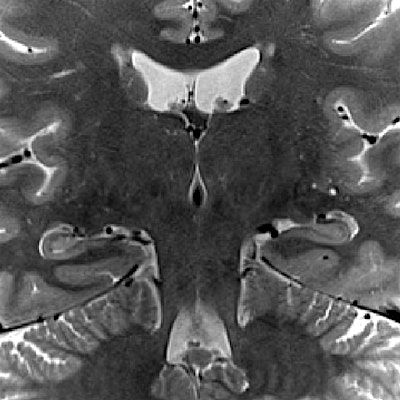

This workshop will provide an introduction to the Hippocampal Subfield Group (HSG) harmonized protocol for subfield segmentation in the hippocampal body, with hands-on training led by experts.

May 8, 9:30 am - 4:30 pm: Instruction and demonstration of the steps for the HSG harmonized protocol for subfield segmentation in the hippocampus body, including time to practice and gain direct feedback from experts in the room.